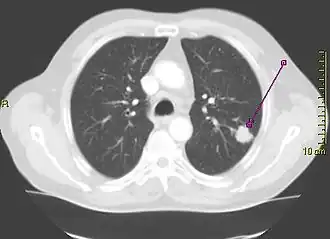

Computed tomography of the chest

Computed tomography of the chest or chest CT is a group of computed tomography scan protocols used in medical imaging to evaluate the lungs and search for lung disorders.

Contrast agents are sometimes used in CT scans of the chest to accentuate or enhance the differences in radiopacity between vascularized and less vascularized structures, but a standard chest CT scan is usually non-contrasted (i.e. "plain") and relies on different algorithms to produce various series of digitalized images known as view or "window". Modern detail-oriented scans such as high-resolution computed tomography (HRCT) is the gold standard in respiratory medicine and thoracic surgery for investigating disorders of the lung parenchyma (alveoli).